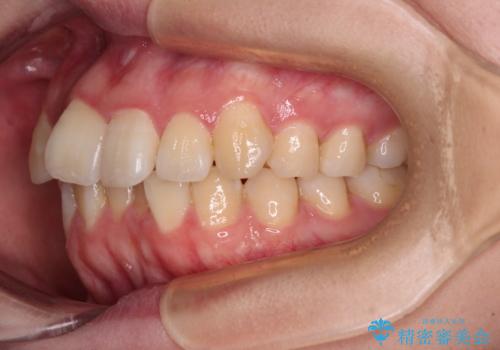

【モニター】八重歯を片側の抜歯矯正で治す メタルブラケット装置

- 八重歯とずれた正中を気にして来院された患者様です。

非抜歯矯正ではデコボコを解消することでより口元が突出する可能性があるため、上顎右右側の小臼歯1本の抜歯を行い、ワイヤー装置による矯正治療を行うこととしました。

お仕事の予定を調整しやすく、平日の昼の時間帯に通院可能であったので、非常にスムーズに治療を進めることができ、1年半で無事に治療を終えることができました。